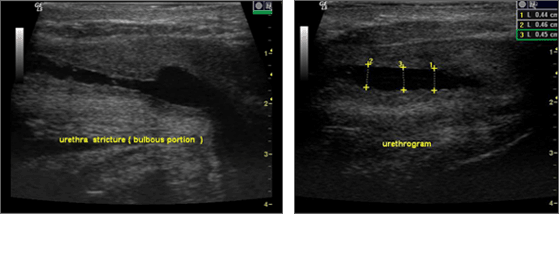

¿äµµÇùÂø Ȧ·¾(HoLEP)¼ö¼ú Àü °Ë»ç Ç׸ñ